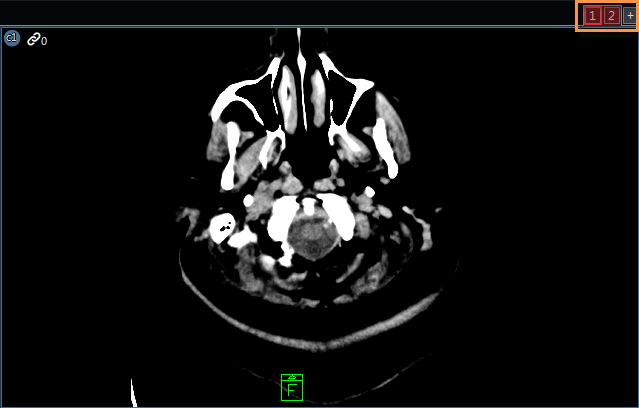

A virtuális monitor egy elrendezésben van definiálva, de fizikailag nem létezik a munkaállomáson. A virtuális monitorok (alább kiemelve) a képnézegető terület jobb felső sarkában találhatók. Példa arra, hogy amikor virtuális monitorok jelennek meg, a kifüggesztési protokoll két monitort használ, amikor csak egy monitorral rendelkező munkaállomáson alkalmazzák. A második monitoron alkalmazott elrendezés létrejön és inicializálódik, de mivel csak egy monitor létezik, azt nem lehet leképezni. Virtuális monitor létrehozásához válassza ki a jobb felső sarokban található + elemet (kiemelve).